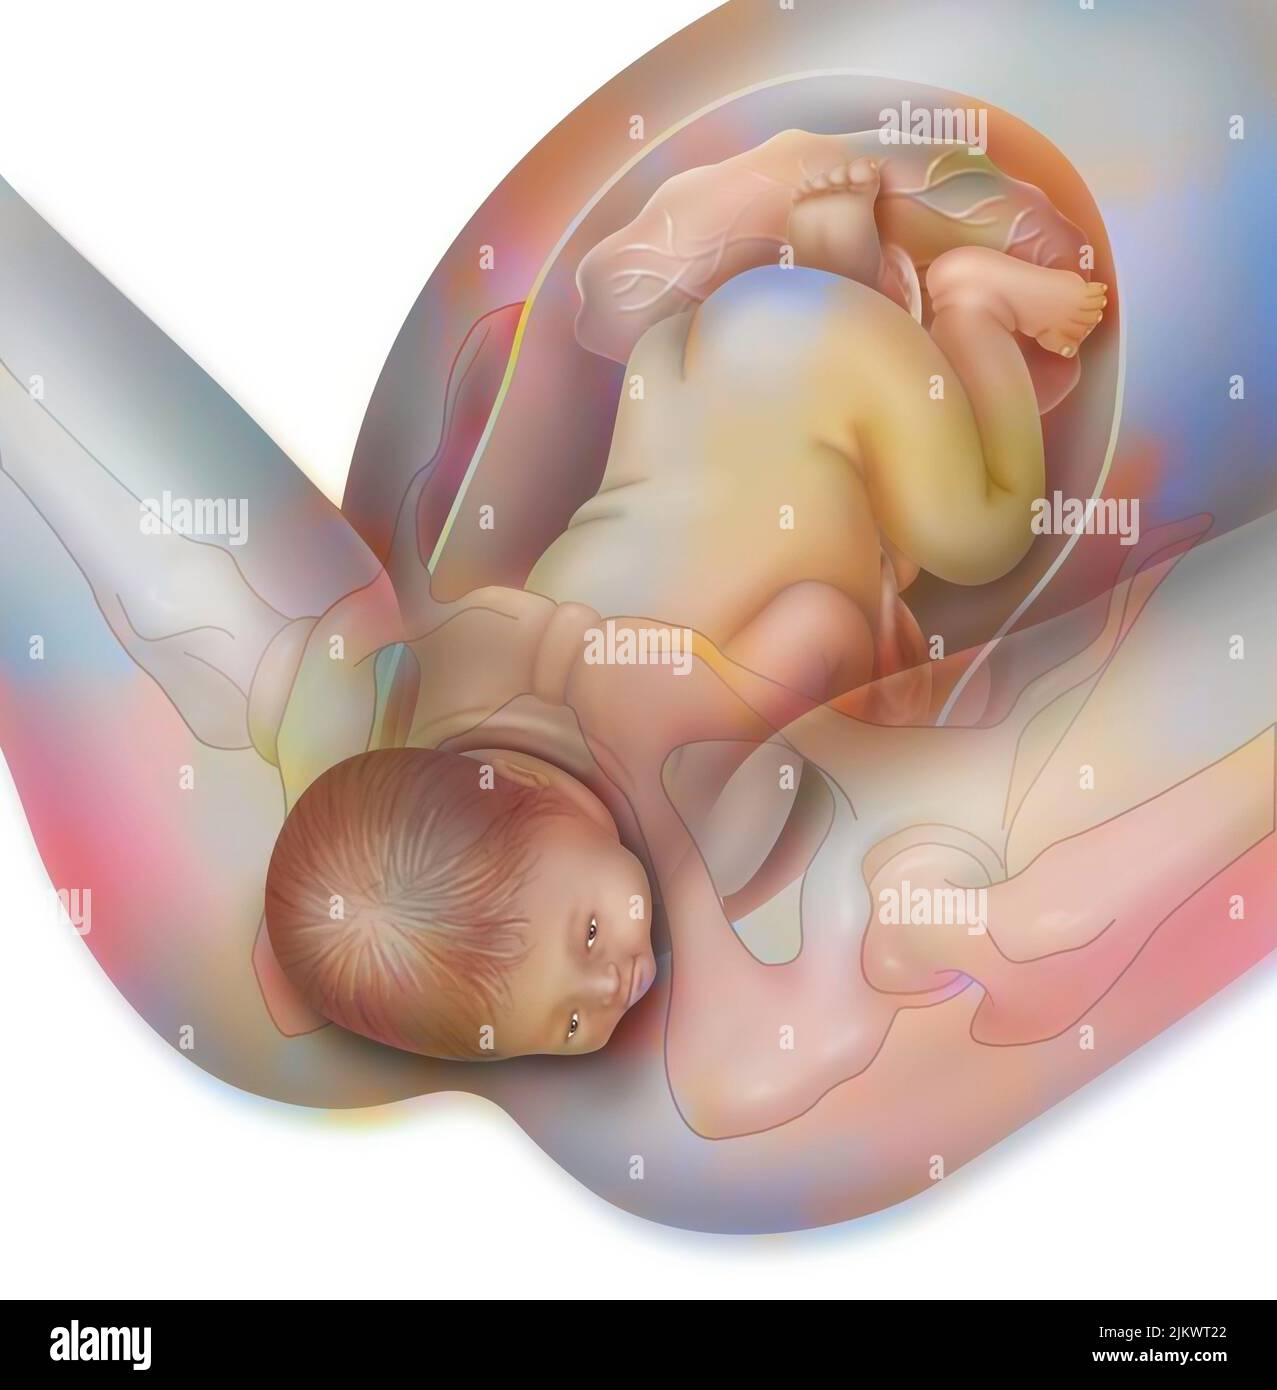

RF2JKWRMG–Thérapie génique : introduction de rétrovirus pour modifier les cellules de la moelle épinière mutées d'un nouveau-né.